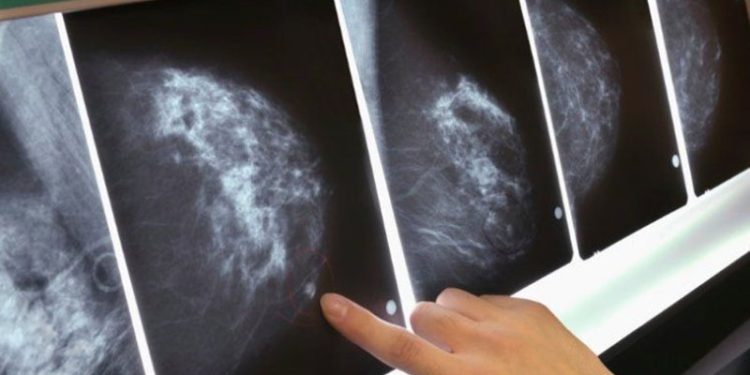

‘Meme Kanseri Farkındalık Ayı’ kapsamında açıklamalarda bulunan Emsey Hospital Onkoloji Uzmanı Prof. Dr. Hakan Karagöl, Türkiye’de her 8 kadından birinin meme kanserine yakalandığına dikkat çekti.

Prof. Dr. Hakan Karagöl, meme bölgesinde ele gelen ağrılı- ağrısız bir kitle veya kalınlaşma olması, meme bölgesi cildinde renk veya biçimsel değişikliklerin olması, bu bölge cildinde yara gelişmesi, meme ucunda çekilme veya meme ucundan akıntı olması en sık rastlanan bulgular arasında olduğunu ve durumlara gelmeden düzenli kontrollerin yapılması gerektiğini söyledi. Kanserin mikroskopik yapısı da genel olarak erkek ve kadın meme kanseri hastalarında benzer olduğunu belirterek meme kanseri farkındalık ayı sebebiyle değerlendirmelerde bulundu.